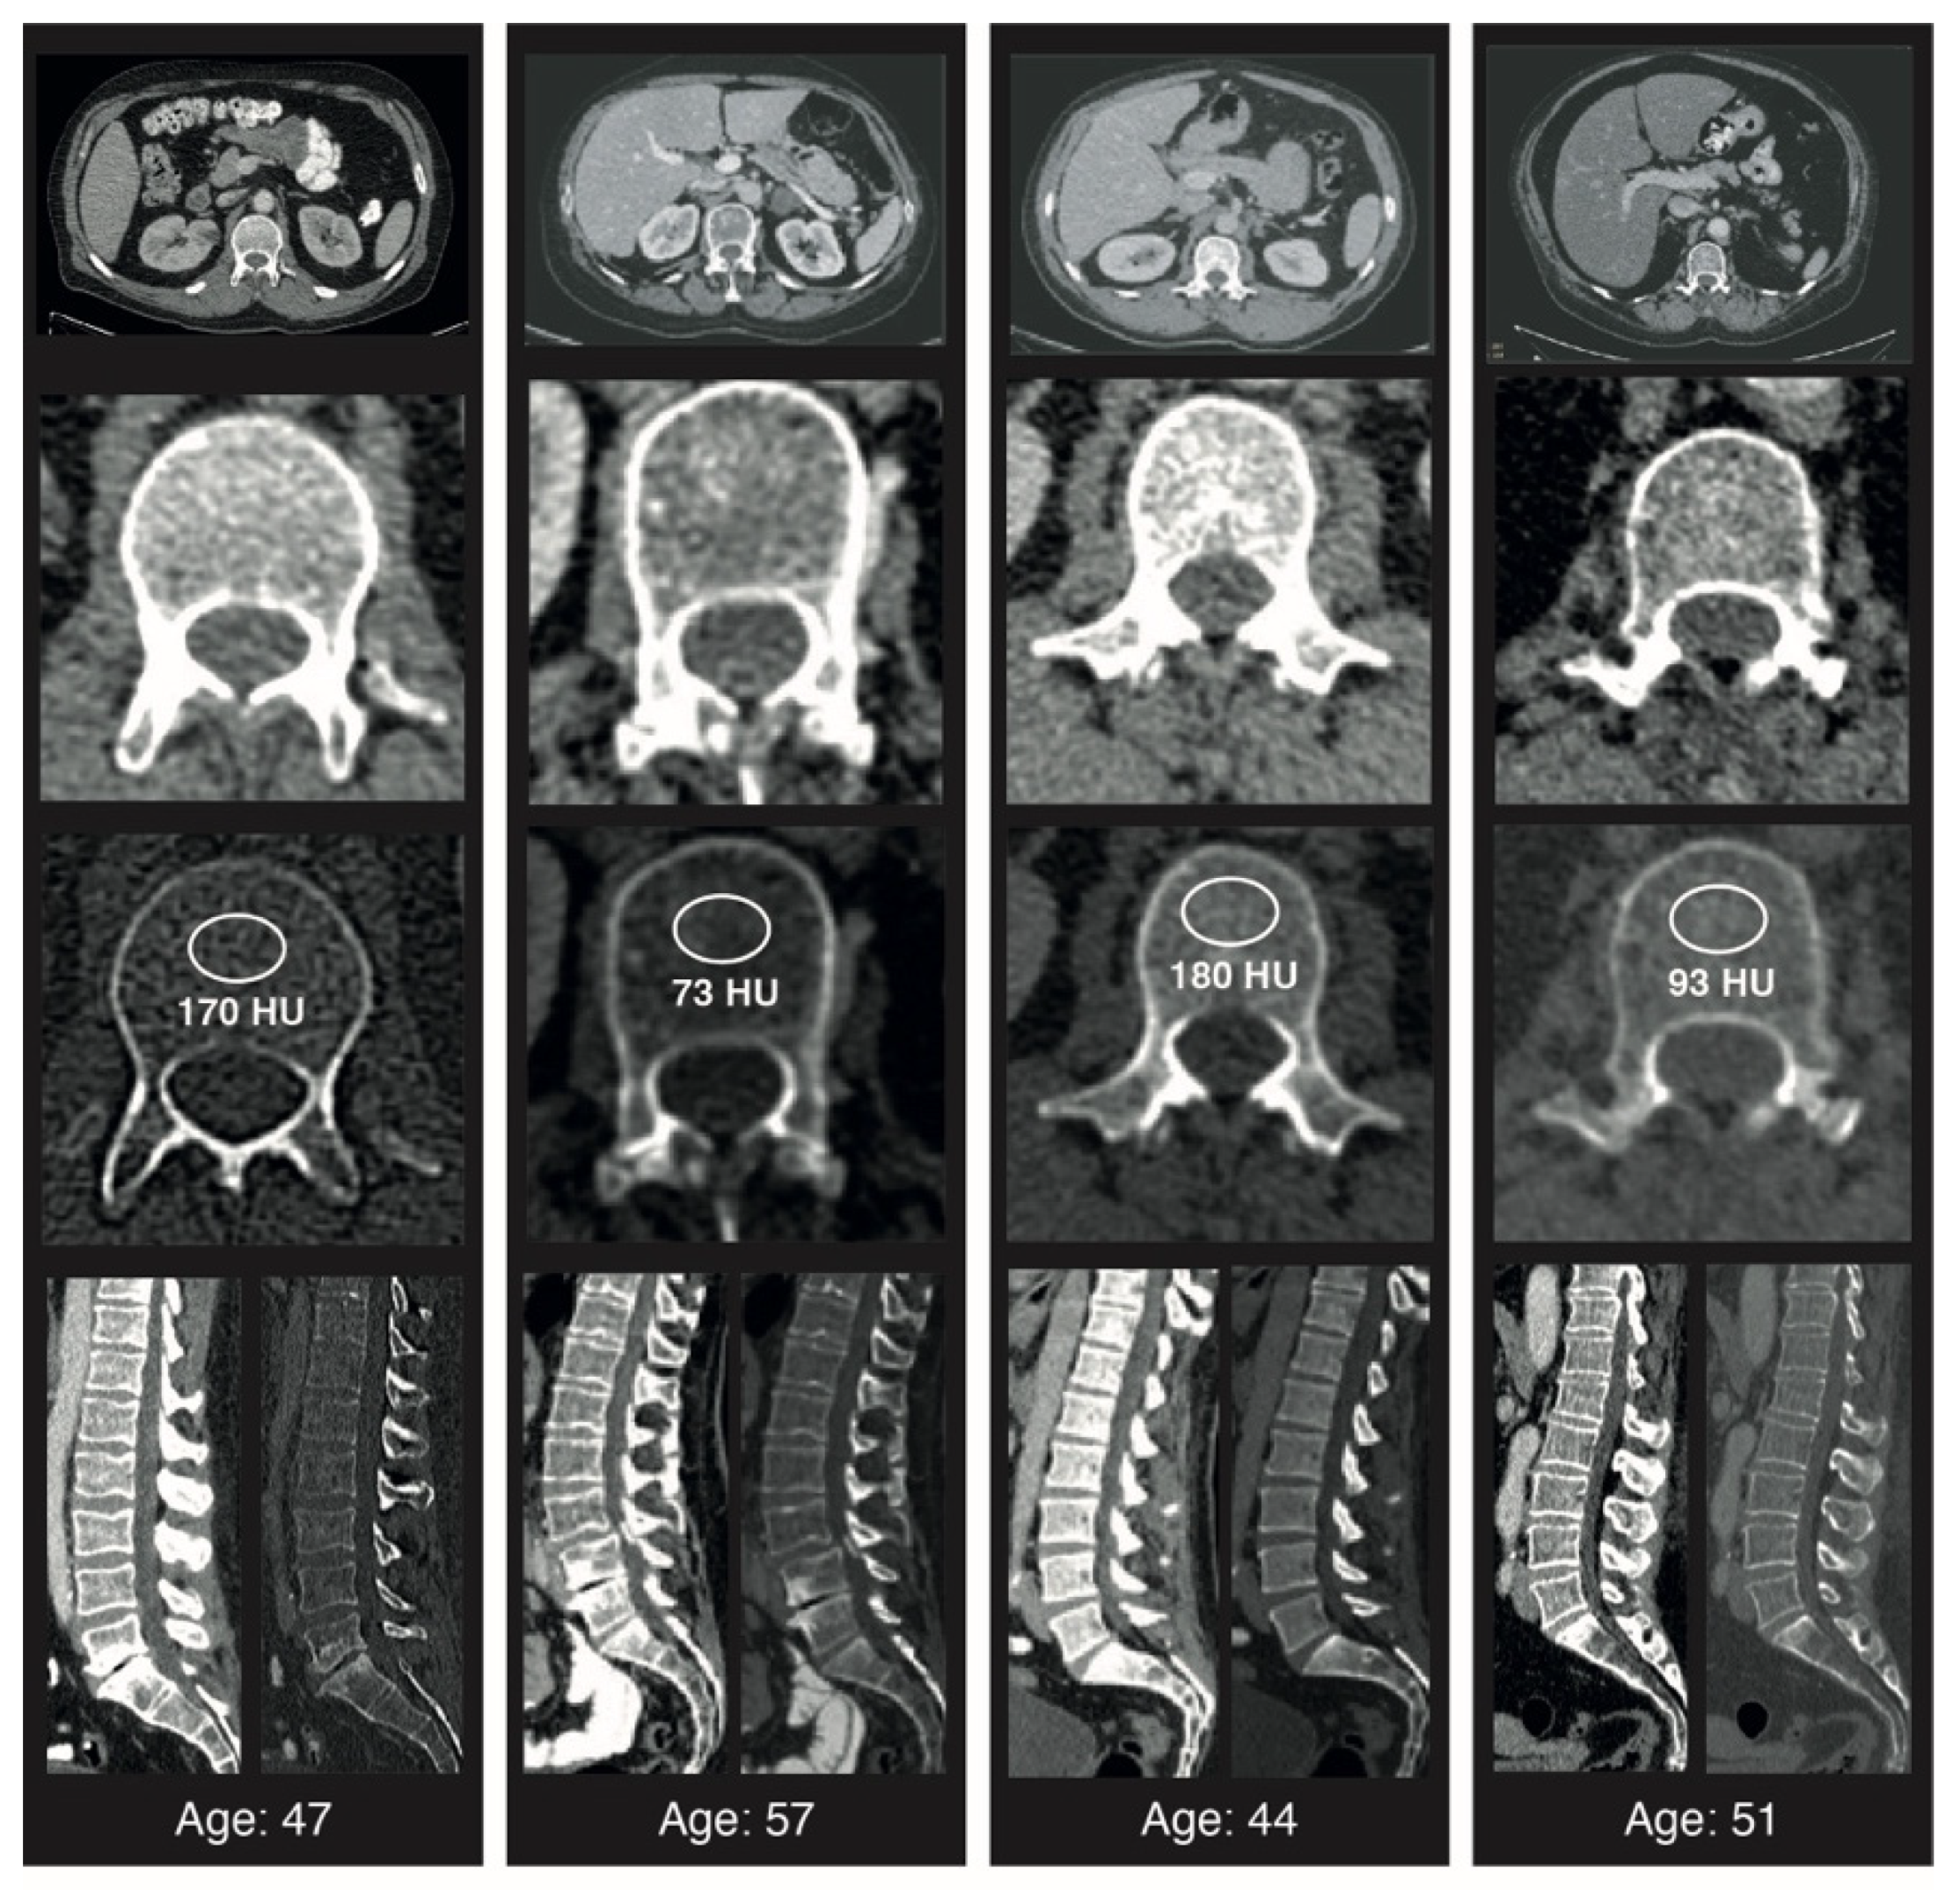

Throughout data acquisition, the radiologist was blinded to all patient characteristics, treatment history, and OS. Figure 1 illustrates exemplary measurements in patients with high and low BMD.

Figure 1. Examples of trabecular L1 attenuation assessment at CT. Transverse (axial) CT scans at the L1 level in adult patients of varying ages and with different average Hounsfield units at the time of diagnosis. Standard placement of the region of interest (ROI) for trabecular attenuation measurement and the mean Hounsfield unit value within the ROI are shown. Sagittal reconstructions with soft tissue and bone windows are shown.